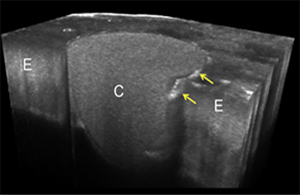

4.CAD/CAMレジン冠の辺縁適合性評価

補綴治療においてクラウンの辺縁適合性は長期的な予後に直結する重要な因子である。本研究では、CAD/CAMで作製したレジン冠の辺縁適合性をSS-OCTなどの非侵襲的手法で評価した。光学断層画像により、クラウンと支台歯との界面を破壊せずに精密に測定することが可能となり、臨床における補綴物の品質管理や設計改善に寄与すると考えられる。

<参考文献>

Zeng C, Tabata T, et al. Clin Oral Investig. 2025;29(3):158-16

③ 修復物の内部・辺縁適合性評価

修復物の長期的な予後には適合性は極めて重要です。波長掃引型光干渉断層計(SS-OCT)、レーザー顕微鏡、シリコンレプリカ法などを用いて適合性を多角的に評価しています。これらの分析を通じて、各種CAD/CAMシステムや設計パラメータが適合精度に与える影響を定量的に解明し、より精密な修復治療の実現を目指しています。